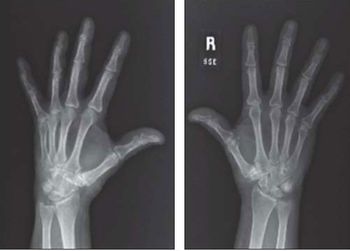

Alpine skiing, snowboarding, bobsledding, ice hockey … the ongoing Winter Olympics in Sochi serve as a cold reminder that injuries plague athletes around the world. Test your knowledge of common sports injuries here.

Bone problems run the gamut from low bone density and osteoporosis to sports and exercise injuries to congenital disorders. Take this week’s photo quiz to test your knowledge of bone disease and related concerns.